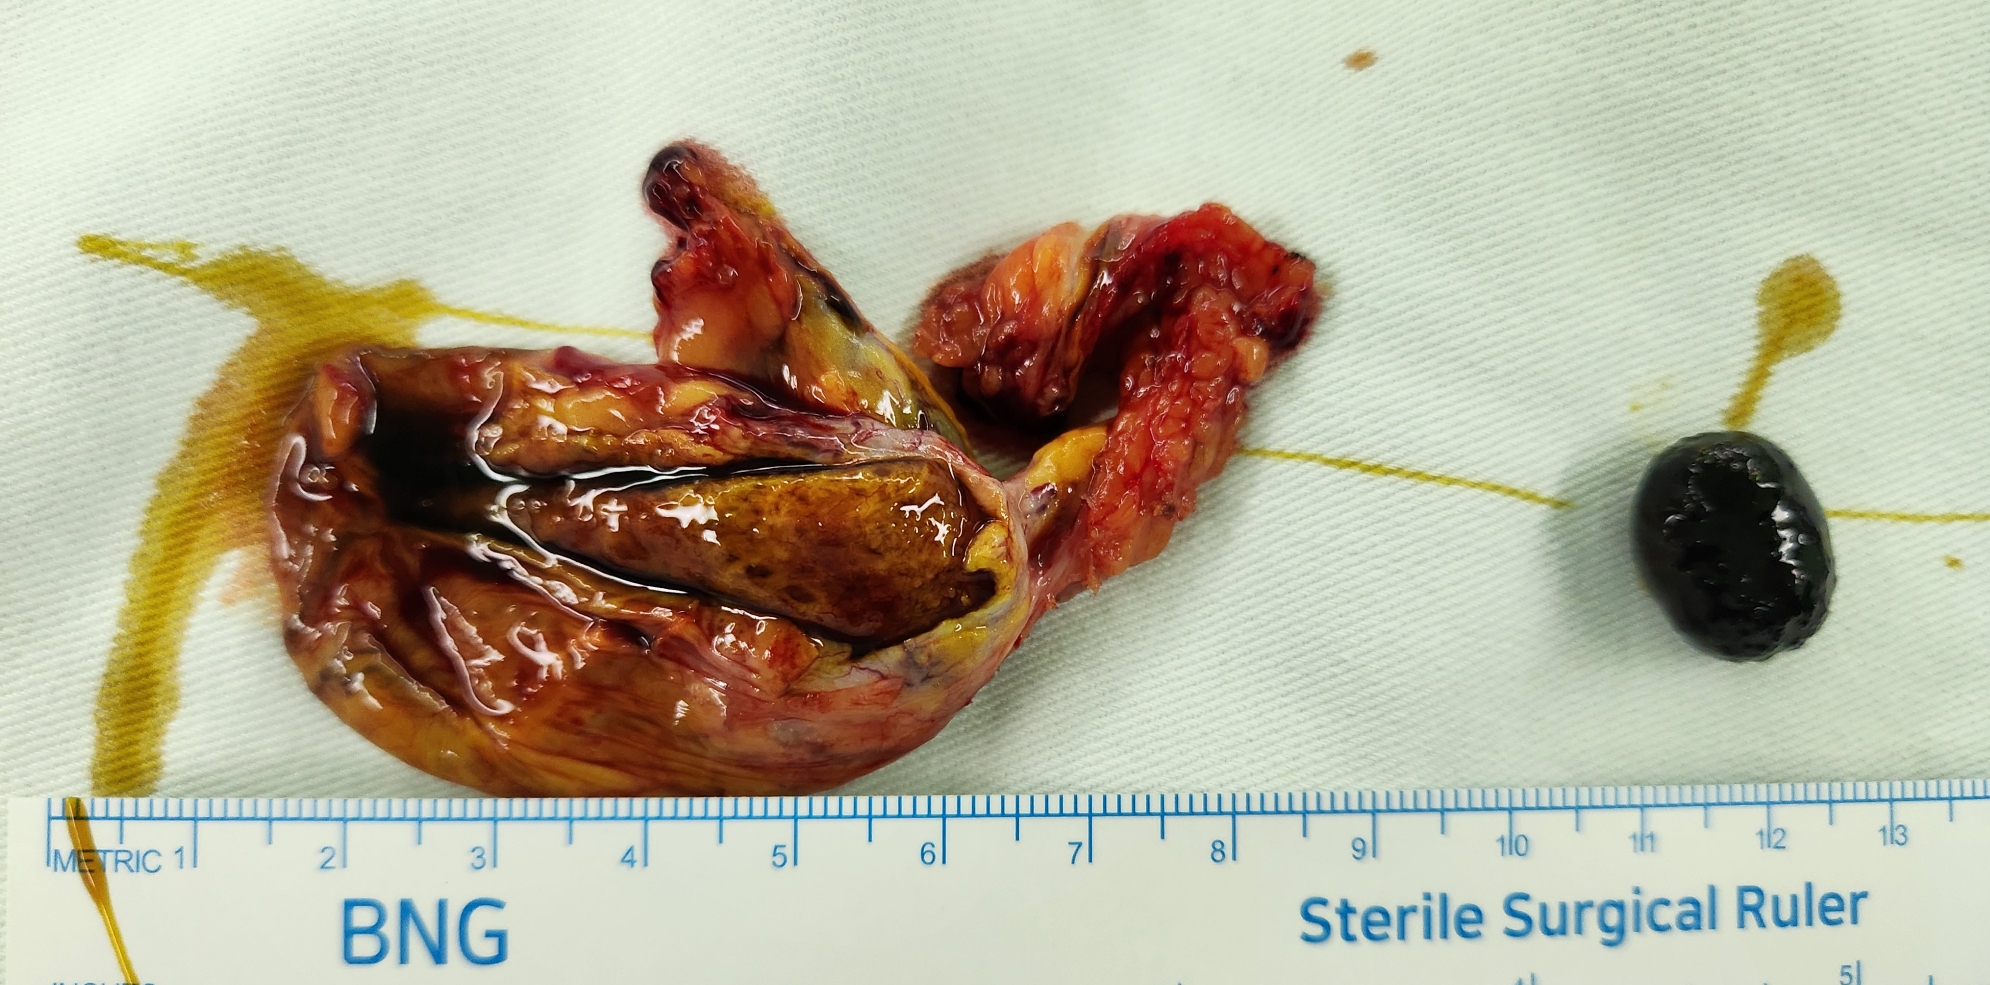

소화불량으로 개인병원에서 초음파 시행후 담석으로 수술 위해 제 외래로 오셨던 분입니다.

방금 단일공 복강경 담낭절제술을 시행했습니다.

수술은 30분 걸렸습니다.